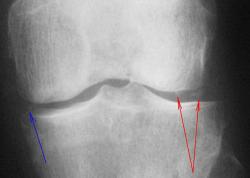

Женщина 75 лет. Жалуется на эпизоды острой боли в передне-внутреннем отделе левого коленного сустава при ходьбе, сопровождающиеся последующими болями в течение 1-3 дней.

И так, что вижу.

1. По всей видимости, необходимо иметь в виду феморо-пателлярный артроз. Конечно, мы не можем оценить ширину суставной щели в феморо-пателлярном суставе, так как боковой снимок сделан не в строгой боковой проекции и суставная щель, как таковая, не дифференцируется. Но можно заподозрить наличие субхондрального склероза - помечен красными стрелками и мелкие субхондральные кистовидные (точечные) просветления - желтые стрелки.

2.Оценивая ширину суставной щели необходимо отметить её неравномерность по ширине - некоторое расширение в латеральных отделах-красные стрелки, по сравнению с медиальными отделами желтые стрелки. Почему расширение латерально, а не сужение медиально? Медиально конгруентность суставных поверхностей сохранена, латерально - конгруентность нарушена - некоторая клиновидность. В области латерального мыщелка б/берцовой кости "намечается" субхондральный склероз - зеленые стрелки.

На фоне суставной щели латерально определяются локальные уплотнения - красные стрелки - локальные обызвествления сумочно-связочных компонентов сустава (по С.А. Рейнбергу), но по всей видимости, это локальные отложения солей Са в "травмированном" мениске, что может свидетельствовать о функцинальной несостоятельности последнего. Точечное уплотнение дифференцируется и медиально - синяя стрелка.

3.Оценивая межмыщелковые возвышения, можно констатировать, что латеральное межмыщелковое возвышение, "кажется несколько больше" (по сравнению с медиальным). Определяется "заострение" и "деформация" вершины латерального межмыщелкового возвышения за счет локального окостенения связки - сиреневая стрелка, что косвенным образом свидетельствует о функциональной несостоятельности этой связки.

4. При анализе проксимального эпи-метафиза б/берцовой кости, локальные участки остеопороза, отмеченные стрелками, связаны, по всей видимости, именно с функциональной недостаточностью мениска и связки, а также с наличием феморо-пателлярного артроза, что функционально выразилось в "недогрузе" латеральных отделов коленного сустава, (возможно даже из-за болевого синдрома, не исключается "подсознательная разгрузка"), и переносе "нагрузки на медиальные отделы.

Уважаемый Валентин Львович всё отлично отметил, я бы хотел добавить, что контуры субхондральной пластинки медиального отдела больше берцовой кости не чёткие, несколько даже волнистые, скорее всего значительные изменения мениска, как следствие болевые ощущения. Ждём МРТ

С точки зрения рентгенолога традиционной ориентации, на рентгенограммах коленного сустава из существенных изменений стоит отметить частичное обызвествление обоих менисков (больше латерального) и субхондрально расположенный линзообразной формы участок то ли остеопороза, то ли остеолиза (лучше виден в задней проекции). Артроза у старушки конечно нет!